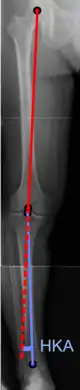

The degree of varus or valgus deformity can be quantified by the hip-knee-ankle angle,[25] which is an angle between the femoral mechanical axis and the center of the ankle joint.[26] It is normally between 1.0° and 1.5° of varus in adults.[27] Normal ranges are different in children.[28]

Hip-knee-ankle angle by age, with 95% prediction interval.[28]